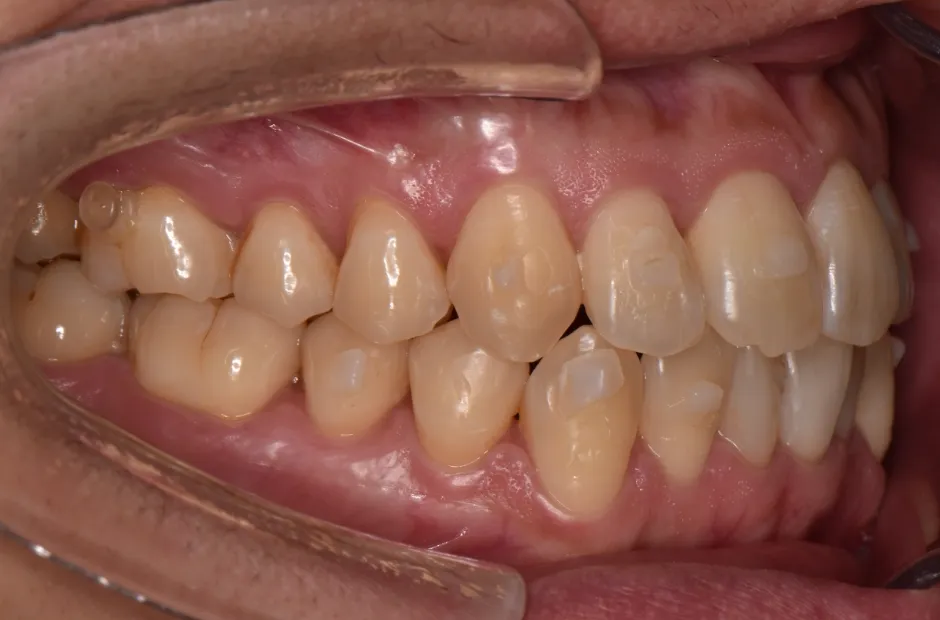

叢生

| 診断名・主訴 | 叢生 |

|---|---|

| 年齢・性別 | 43歳・女性 |

| 治療期間・回数 | 2年7か月 27回 |

| 治療に用いた主な装置 | 舌側矯正 |

| 抜歯部位 | 両顎4,4 |

| 治療費 | 100万円(税抜) |

| リスク・副作用 | 装置による違和感・疼痛・歯肉退縮・歯根吸収・虫歯のリスクなど |

治療前

治療後